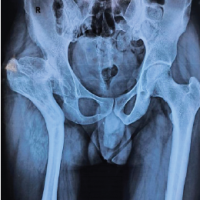

An 8-year-old Hispanic male with no significant medical history presented with bilateral hip pain of eight out of ten on the visual analog scale. He had been followed at a pediatric orthopedic clinic for nearly a year for magnetic resonance imaging (MRI) findings suggestive of bilateral LCP disease at the early fragmentation stage. Lesions were somewhat symmetrical, so a rule out of Meyer’s dysplasia and genetic counseling was done accordingly. Imaging showed 10–15% non-enhancement in the left hip and 10% in the right hip, with more severe avascular necrosis on the right. Scant effusions were noted, without signs of arthrosis or collapse. Given his age and benign diffusion-weighted MRI findings, he was managed conservatively with non-steroidal anti-inflammatory drugs, activity modification, and rest for over a year. Due to persistent pain and unchanged imaging findings, he was referred to our Hip Preservation Clinic. On examination, a functional waddling gait was noted. Bilateral hip flexion was 0–100°, with pain on pure flexion. Internal rotation with flexed hips measured 15° with pain, and external rotation was 40° bilaterally. Anterior impingement and apprehension tests were positive bilaterally. A mucopolysaccharidosis and Sickle Cell panel was ordered and returned negative. Given the benign clinical picture, conservative management continued, including close observation and a 2-month course of physical therapy. At a 4-month follow-up, the patient reported no improvement in pain, and his physical exam remained unchanged. Repeat MRI revealed an under-covered femoral head with a chondral defect partially covered by functional cartilage (Kerboul Grade II) (Fig. 1). A full radiographic workup showed findings consistent with borderline hip dysplasia (Fig. 2), prompting the recommendation for bilateral triple pelvic osteotomies (PAO).